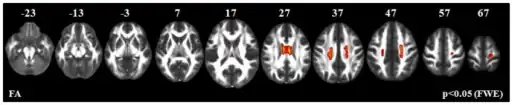

| Juvenile Primary Lateral Sclerosis has an autosomal recessive pattern of inheritance, meaning both copies of the gene in each cell are altered. | |